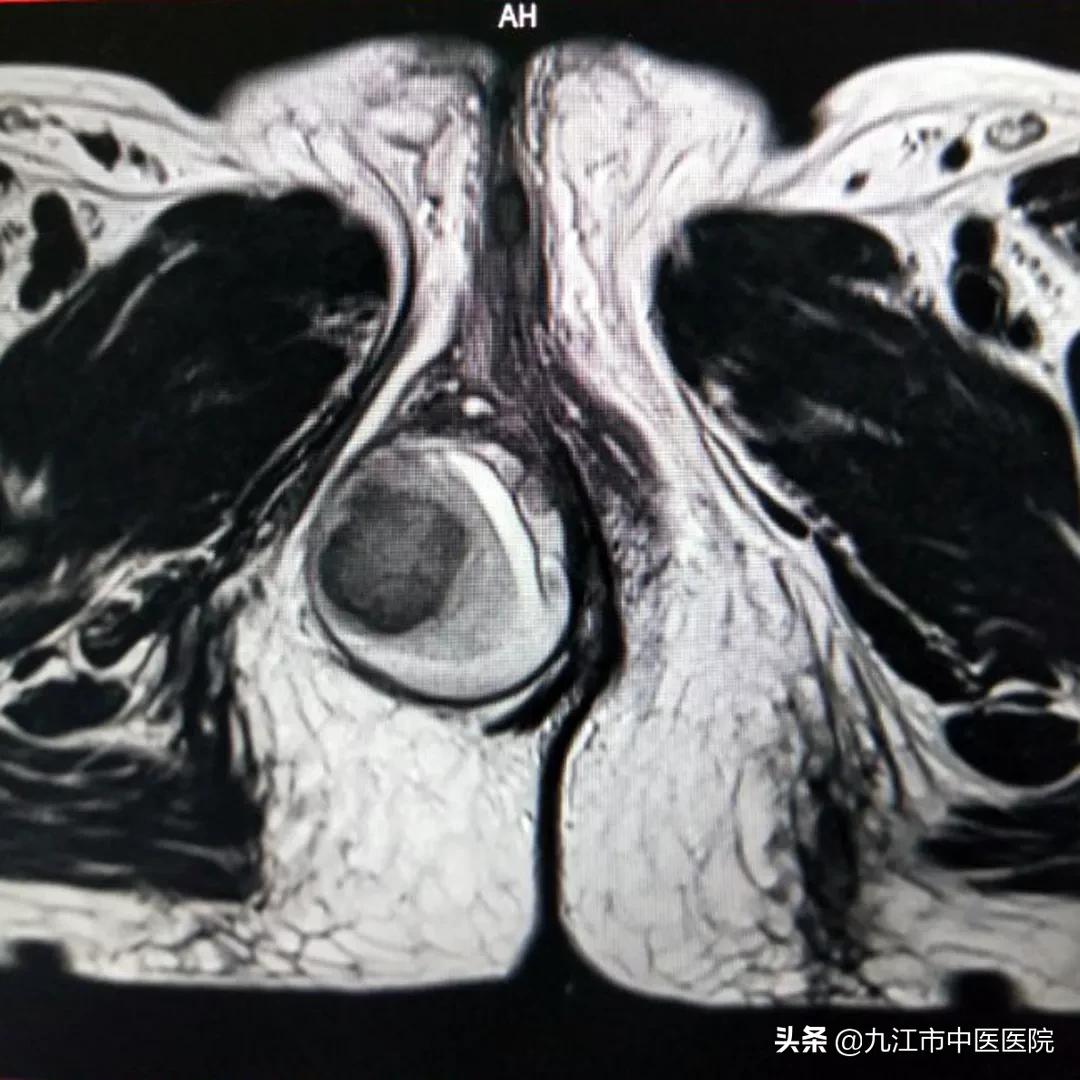

据经管医生桂慧俐介绍,该患者因肛旁肿痛一天来院就诊,自诉既往有便秘史、痔疮史,一天前因大便努挣出现肛旁会阴处包块,肿痛难忍。结合盆腔磁共振检查发现肿块内血流信号影,肿块直径大小约5cm左右,边缘界限清晰,排除肛周脓肿,诊断为会阴血肿可能。